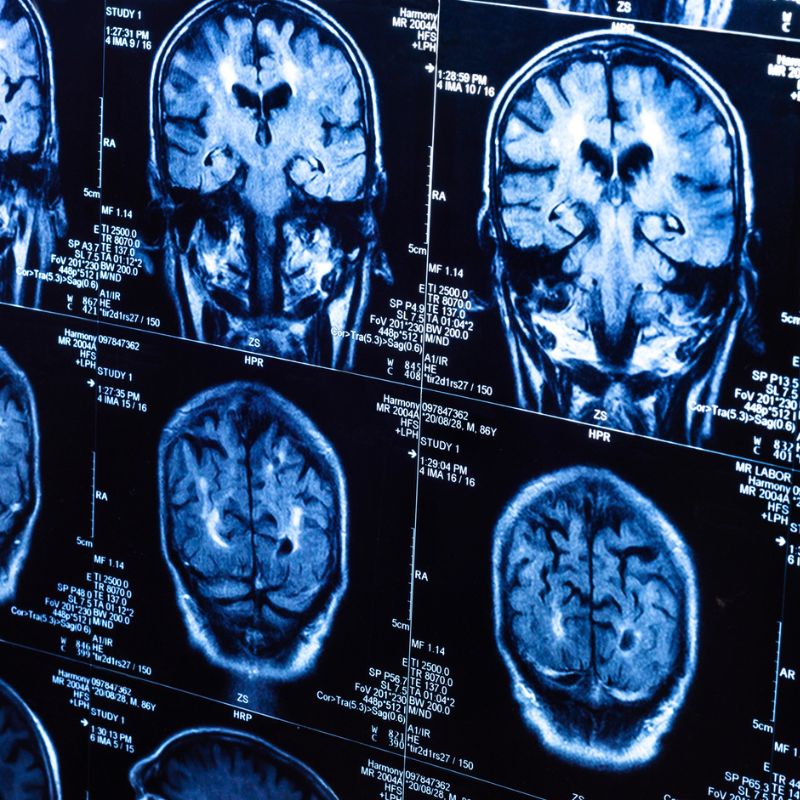

L’article examine le potentiel de l’hypnose clinique comme outil thérapeutique capable de stimuler la neuroplasticité, c’est-à-dire la capacité du cerveau à se réorganiser et à créer de nouvelles connexions neuronales.

Les auteurs s’appuient sur 30 études publiées entre 2000 et 2024 portant sur l’imagerie cérébrale, la réhabilitation psychologique et les thérapies intégratives.

Ils révèlent que l’hypnose semble agir sur la connectivité neuronale, la mémoire et même l’expression des gènes, ce qui favorise la régulation émotionnelle, la restructuration cognitive et l’adaptation biologique.